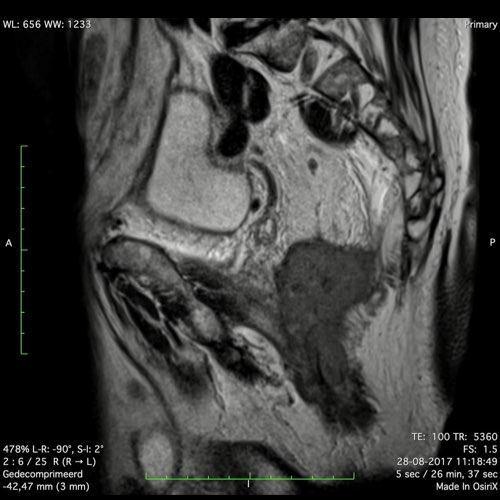

Hình ảnh

Các hình ảnh được cung cấp cho thấy ung thư biểu mô tế bào nhẫn với tình trạng dày lan tỏa thành trực tràng, hình ảnh bia bắn điển hình, và sự xâm lấn mỡ mạc treo trực tràng.